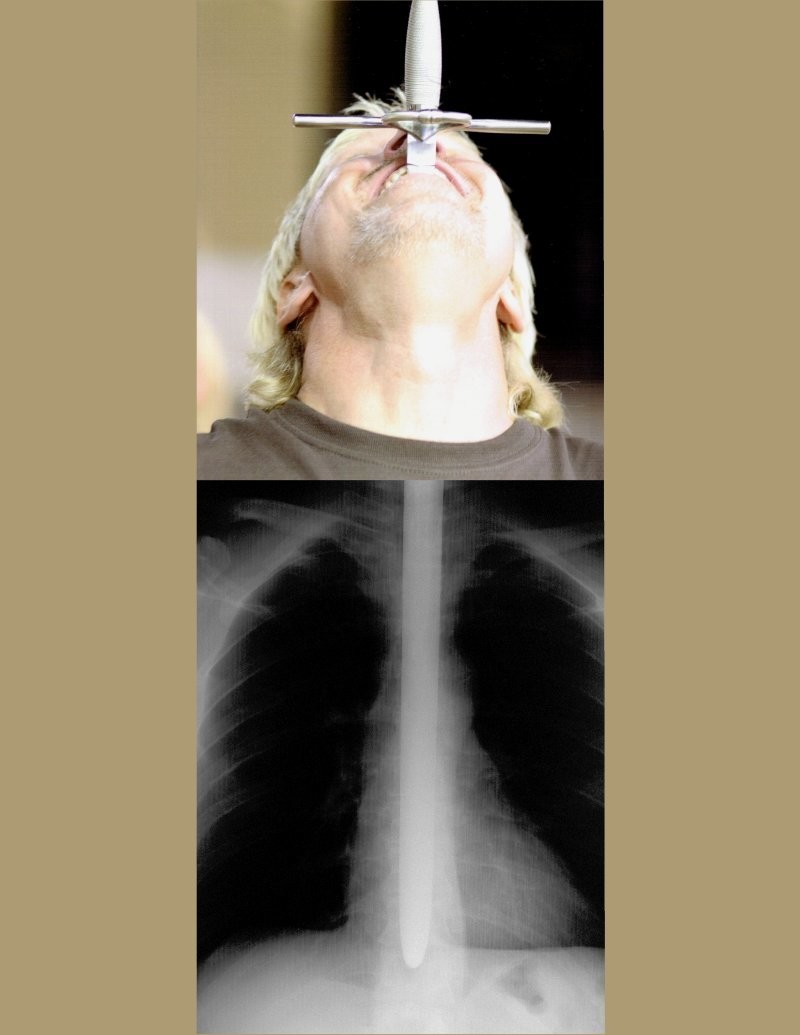

Через пару лет вернулся домой и стал выступать как жонглёр и поглотитель огня. Попутно оттачивая навыки шпагоглотания. В 2001 году он впервые выступил на публике. И понял, что помимо выступлений нужно давать людям и информацию. Ведь шпагоглотание – это не просто система, это искусство и наука, в которой действуют свои законы. Сначала нужно научиться чувствовать подложечную впадину – предельное место погружения лезвия. Затем можно приступать к тренировкам с неопасными предметами. И только предварительно закрепив навык на ложках, кистях и собственных пальцах можно переходить к холодному оружию.

У Дэна на обучение глотать мечи до 15 штук сразу ушло целых пять лет. А сейчас «диета» рекордсмена поражает своим многообразием: на шоу он глотает разные ножи, сабли, кинжалы, палаши. В ход идут даже штопоры и садовые ножницы. А ещё в копилке Дэна есть трюк с глотанием раскалённого меча и целого пучка шпаг.

Искусство некоторые члены ассоциации передают и своим потомкам. И хотя Мейер – настоящая звезда, он не устаёт повторять новичкам, что риск получить травму очень велик. Ведь лезвие проходит в непосредственной близости от жизненно важных органов. И одно неверное движение может привести к летальному исходу.

Тем более что он и сам получал даже на пике карьеры серьёзные травмы, в частности, пищевода. Несмотря на серьёзное изучение темы (Дэн лауреат Шнобелевской премии по медицине 2007 года за изучение побочных эффектов глотания шпаг).